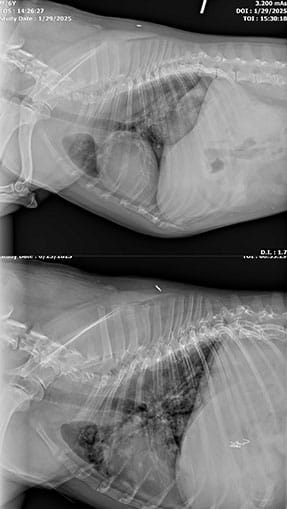

Kima came to me coughing up blood. Her lungs were filled with tumors.

Oncology determined:

• No Western options.

• Euthanasia recommended.

Her family chose Eastern-focused supportive care.

We agreed that if she did not improve quickly, we would pivot.

Within a week:

• no more coughing blood

• appetite returned

Within three weeks:

she was back to walks. Zoomies. Life.